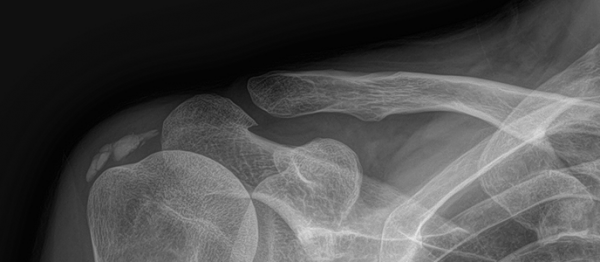

석회쇄석흡인술 페이지 정보 작성자최고관리자 등록일 2025-02-26 17:16 조회22 본문 치료 증상 갑자기 팔 들기 힘듦, 밤에 아픔 나이 / 성별 55세 / 남성 치료내용 석회쇄석흡인술 후 호전 치료기간 2024-11-22 ~ 2025-02-22 null 목록 다음글석회쇄석흡인술 25.02.25 댓글 0 댓글목록 등록된 댓글이 없습니다.